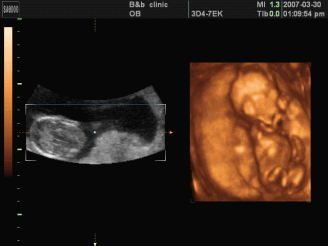

李想丽,女,超声诊断医师,具有执业医师和CDFI医师资格,在某地方医院从事超声工作10余年。曾在兰州大学第一附属医院超声科进修学习。擅长四维超声胎儿畸形筛查、腹部脏器、浅表脏器、妇产科彩超检查。

为了能更准确的检查胎儿是否健康,善懿堂诊所引进了我县首台高端四维彩超,不仅能检查胎儿是否健康,还能为胎儿拍宫内写真,受到了不少准爸妈的青睐。

四维彩超的检查时间有着很大的学问,只有在最佳时间里检查才能获得比较全面的检查效果,一般认为孕20周至28周是四维彩超检查的最佳时间。因为这个时段胎儿的肢体及各主要脏器已经全部发育,而且羊水较适合做胎儿畸形筛查。

1、全方位、多角度观察:四维彩超可以全方位、多角度地了解胎儿在宫内的生长发育状况,能够在早期诊断胎儿先天性身体表面畸形和先天性心脏疾病提供正确的科学依据。

3、胎儿体表检查:四维彩超还可以对胎儿的身体表面进行全面的检查,如唇裂,脊柱裂,脑积水,无脑儿,小头畸形,肾积水、心脏先天畸形、骨骼发育不健全等,提供了准确的科学的依据,并能及早的治疗。

4、实时动态活动图像:可以清楚的展示胎儿在宫内的实时动态活动图像。还可以将宝宝的样子以及动作制作成照片或动态视频,那么就可以让宝宝拥有最完整的0岁相册。